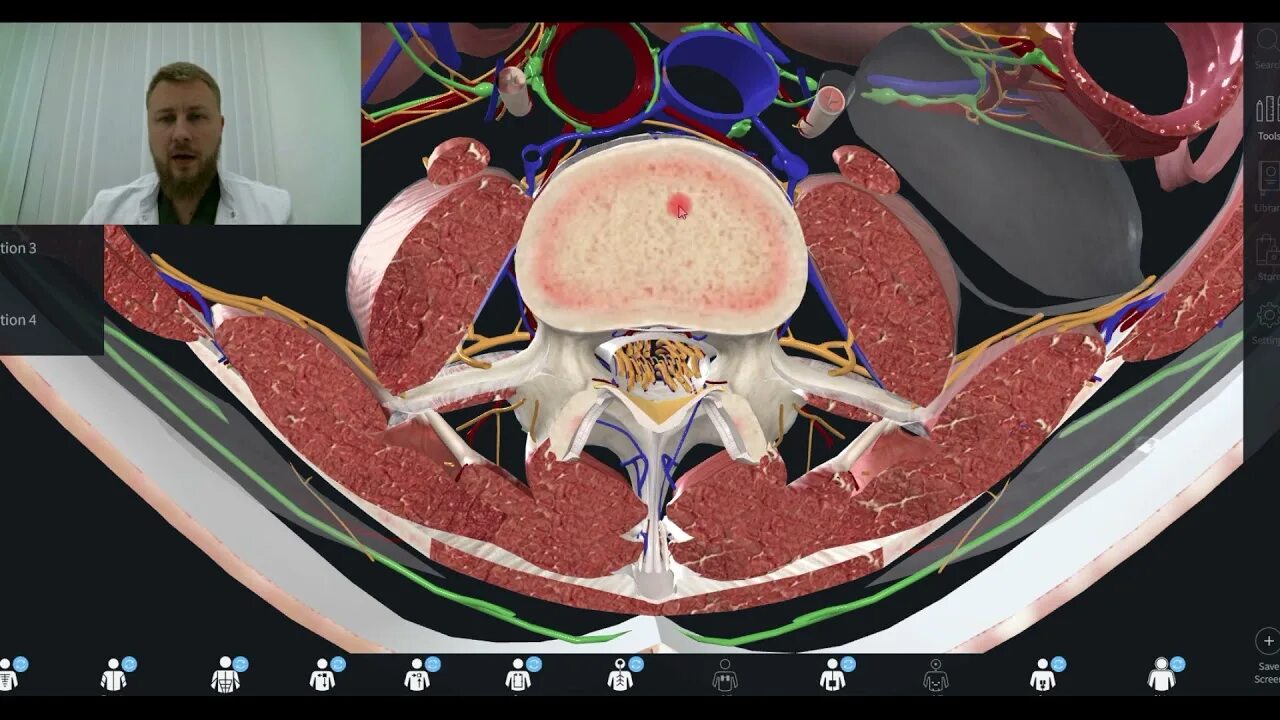

Дифференциальное мрт